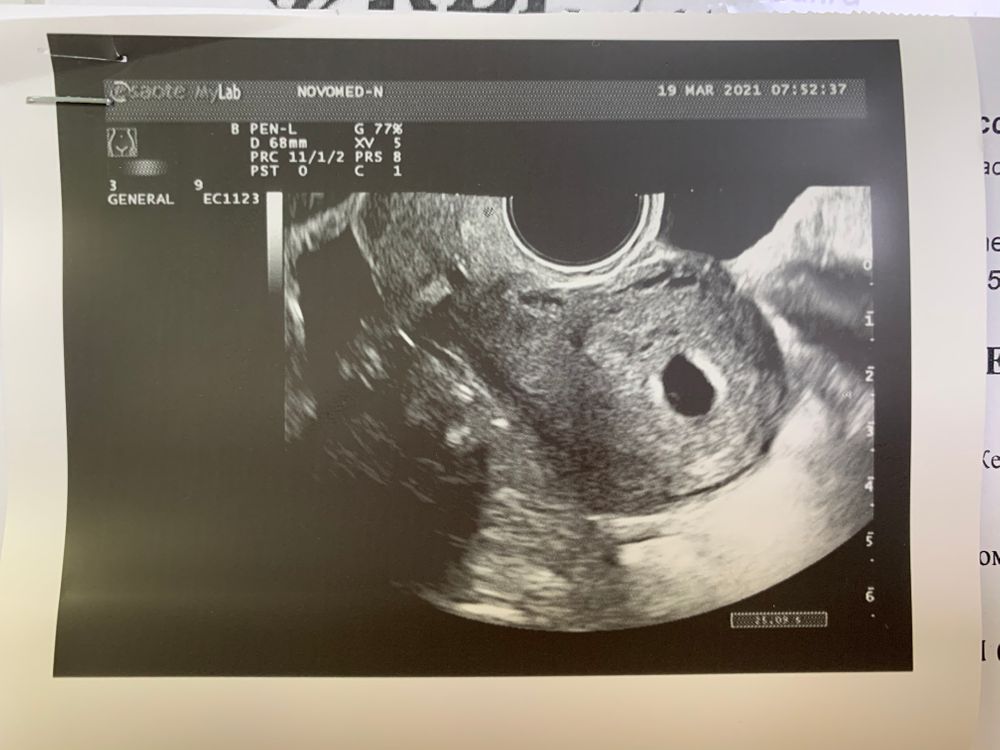

У меня 5 недель и 5 дней по месячным. По узи плодное яйцо на 5 недель 6 дней😁

Врач сказал все соответсвует сроку. Для сердцебиения пока рановато.

Моя крошечка: